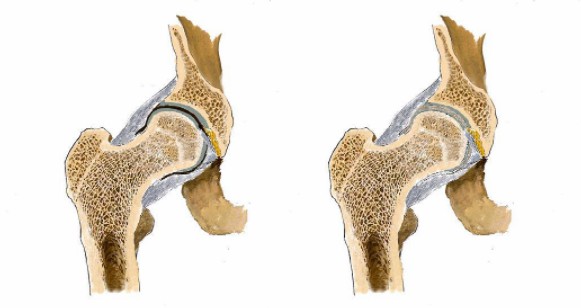

“強(qiáng)直性脊柱炎”是男孩在檢查單上看到的字眼,他知道醫(yī)生想通過檢查確定自己是否得了這個(gè)病。

“無法根治”“病后期致殘”“失去自理能力”……一個(gè)個(gè)關(guān)鍵詞出現(xiàn)在詞條上,男孩有些許目眩,明明只是腿疼怎么就變成了這樣?

男孩繼續(xù)搜索,“強(qiáng)直性脊柱炎會(huì)死嗎?”,詞條出現(xiàn)了“不死癌癥”。

看男孩不說話,醫(yī)生繼續(xù)說道:“你的HLA-B27顯示陰性,如果是陽性就可以確診是強(qiáng)直性脊柱炎,現(xiàn)在只能排查……如果確診是強(qiáng)直性脊柱炎,就要就要及早治療,因?yàn)檫@個(gè)病是不可逆的,我們只能延緩它病程進(jìn)度……”